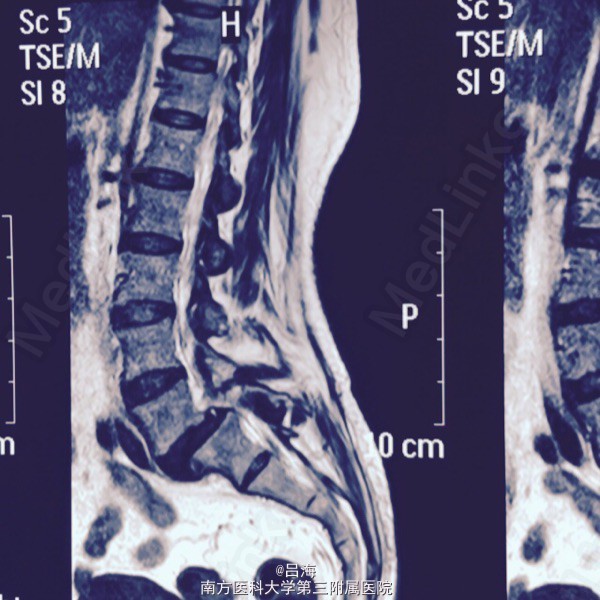

腰痛伴双下肢麻痛无力3年,加重1周。腰椎活动受限,弯腰时明显,间歇性跛行。

下腰压痛,并向双下肢放射,直腿抬高试验阴性。 腰椎DR,CT提示:腰5椎体二度滑脱并峡部裂,椎管狭窄

腰5椎体II度滑脱并峡部裂;椎管狭窄症。 后路腰5全椎板切除减压,滑脱复位,椎间cage植骨融合,经椎弓根内固定术

术后症状缓解 术中要求减压彻底,全椎板切除,显露、减压双侧腰5骶1神经根,撬拨辅助复位,但不强求复位。